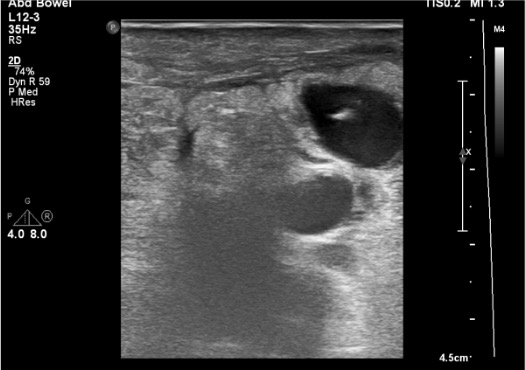

- Gray-scale: hypoechoic/anechoic fluid collection adjacent to femoral artery; may see layered thrombus within sac

- Neck visualization: narrow channel connecting sac to parent artery; measure length and width